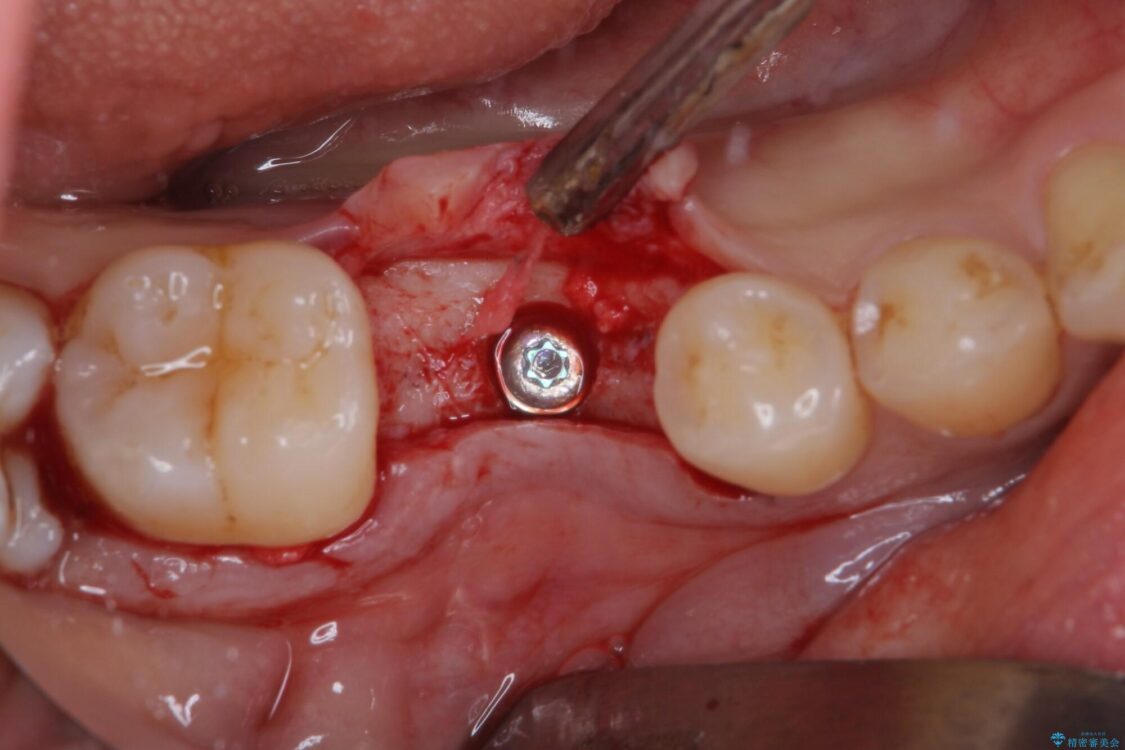

治療途中

• 空いている時間を利用して通院 奥歯のインプラント治療 治療途中画像